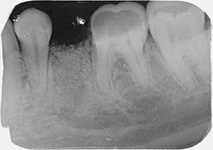

Při ztrátě molárů a premolárů v horní čelisti a jejich náhradě implantáty se často setkáváme s nedostatečnou vertikální nabídkou kosti pod čelistní dutinou, často doprovázenou i nedostatečnou horizontální nabídkou a sníženou kvalitou kosti

(v oblasti 2. premoláru v 50%, v oblasti moláru až v 80% případů nedostatečná kostní nabídka)